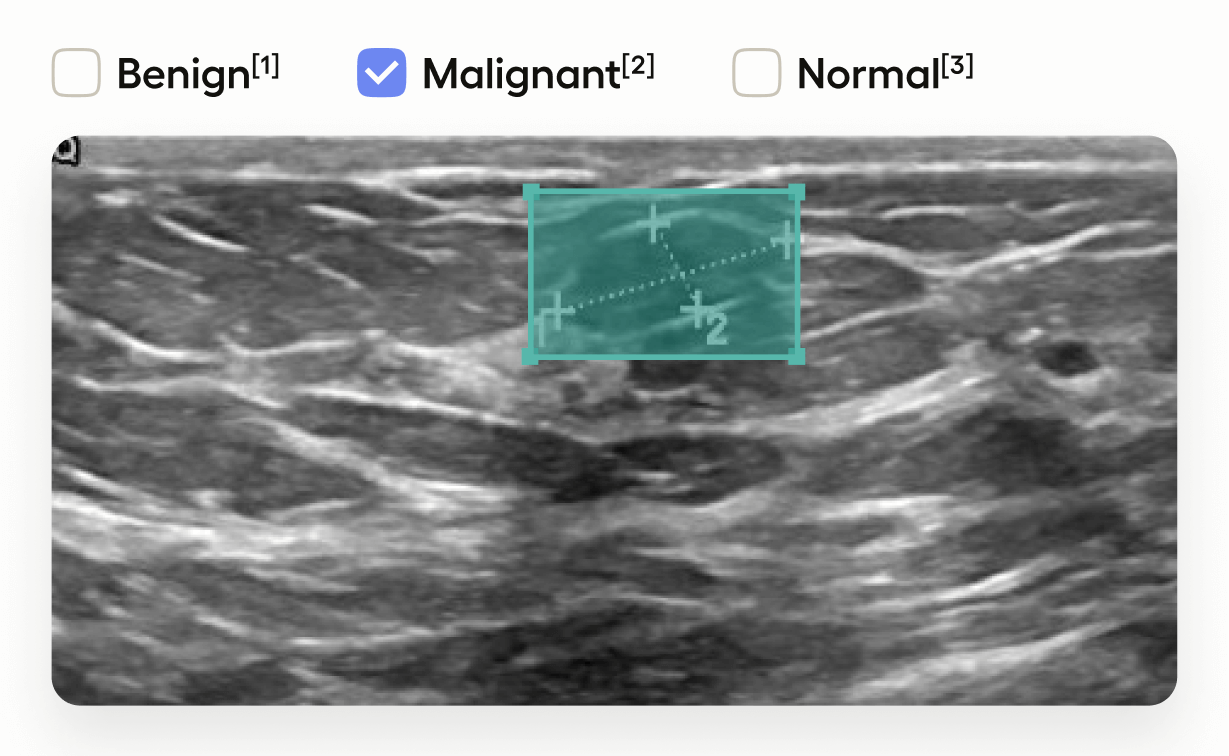

This template interface allows annotators to:

• Draw bounding boxes around areas identified as tumors in the image using the โ€œTumorโ€ label.

• Classify the entire image by selecting one of โ€œBenignโ€, โ€œMalignantโ€, or โ€œNormalโ€.

This setup is useful in medical imaging tasks where you need to localize tumors and also provide an overall assessment of the image.